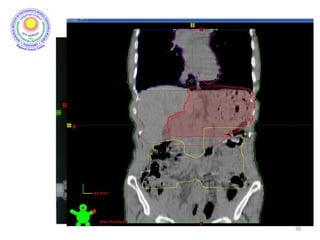

CONTOURING OF TARGET VOLUMES AND

ORGANS AT RISK

24

• Target volume for all gastric cancers would include body of pancreas, full

stomach bed and all regional nodes. Depending on part of stomach

involved, CTV may include also diaphragm, duodenum or lower

esophagus.

• Definition of Target

Volumes

Anastomoses

Gastric bed

Lymph nodes

•Definition of OARs

Kidneys, liver,

lungs, heart, sp

cord

Target and OARs